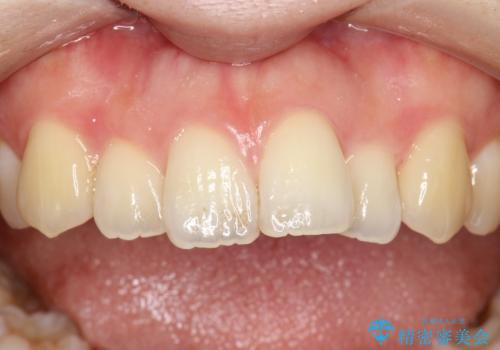

茶渋による汚れをクリーニングできれいに

- 全体の歯にうっすらと茶渋によるステインが見られます。

よく見ると歯自体はあまり黄色くないので、ステインによって歯が黄色く見えてしまっています。

PMTCというクリーニングを行うことでステインは除去できるので、今回はPMTC(エアフロー)の60分コースにて全体のクリーニングを行いました。